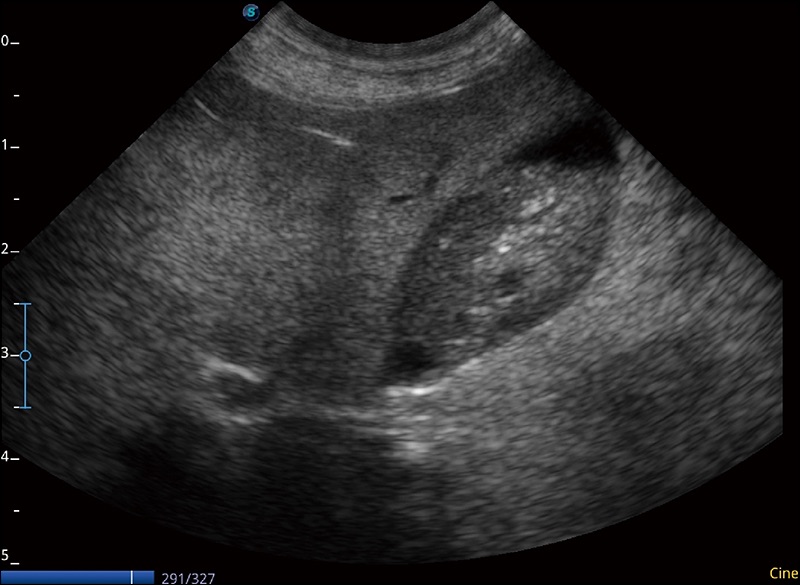

实时宽景成像

可实时观察感兴趣区域和病变位置